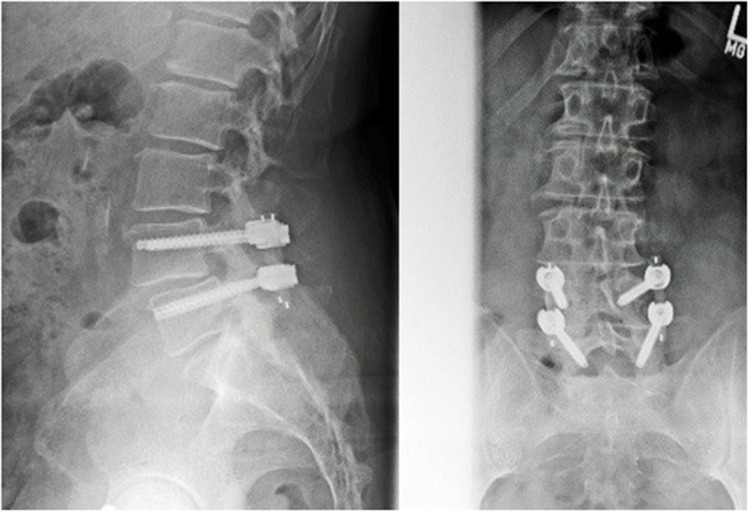

Purpose: The present retrospective study delivers first results after the use of a pedicle based, screw and peek rod system. Emphasis was placed on the ability of the construct to prevent adjacent segment disease at an average of 5 years follow-up by maintaining a certain degree of movement in the index segment. This was evaluated via functional X Rays before and after surgery.

Patients and methods: The cohort comprised 100 patients which received decompressive surgery in one or more segments with dynamic instrumentation for stenosis of the lumbar spinal canal and degenerative spondylolisthesis. We analyzed diagnostic imagery including functional X Rays prior and after surgery as well as cohort demographics such as reoperation rate, complications and overall patient satisfaction.